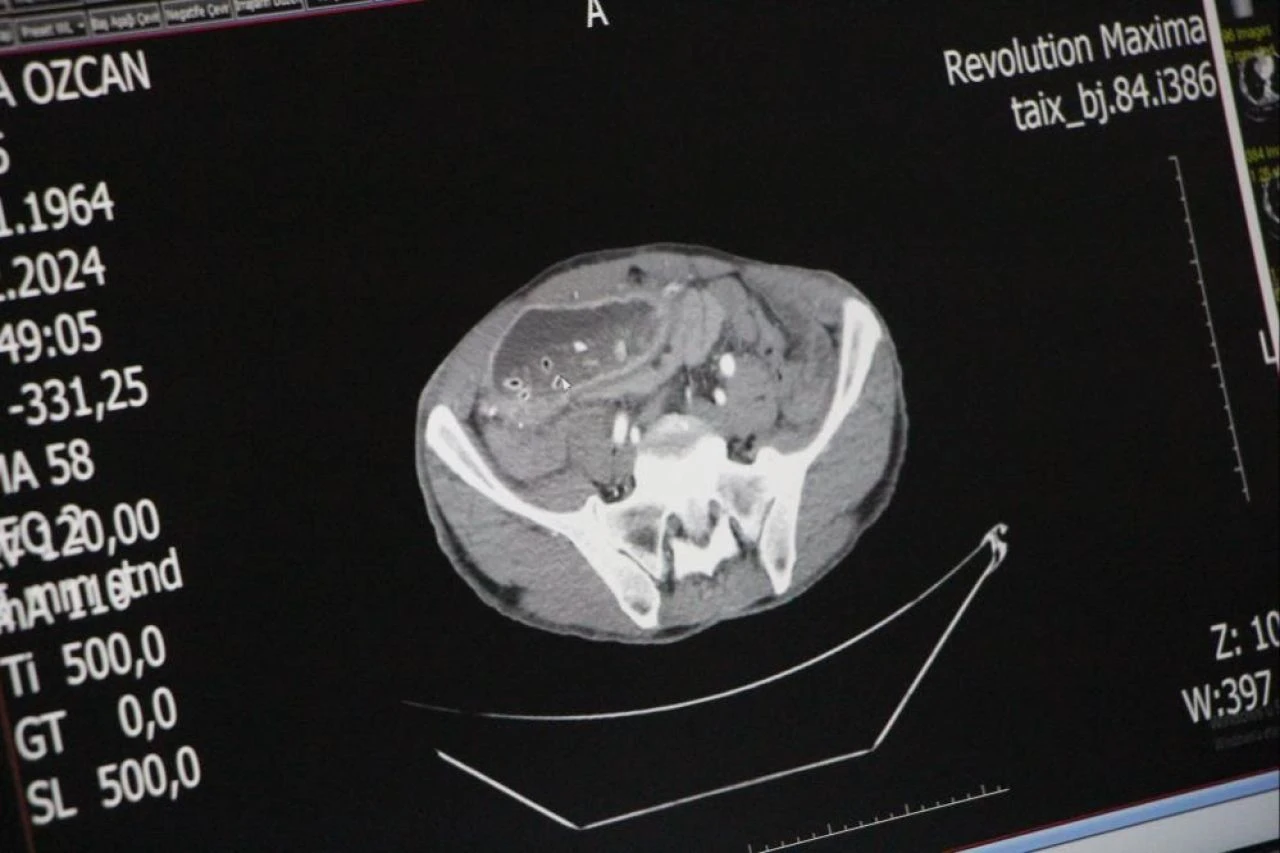

Amasya'da özel bir hastanede yapılan endoskopi ve tomografi çekiminin ardından gerçekleşen ameliyatta Özcan'ın çıkış kısmı daralan midesinin 10 kattan fazla büyüyerek karın boşluğunu sardığı görüldü.

Mide ve karaciğer arasında oluşan doku bandının mideyi ikiye ayırdığını gören Genel Cerrah Doç. Dr. Yavuz Pirhan, ince barsak ile mide arasına yeni bir kanal yaptı.